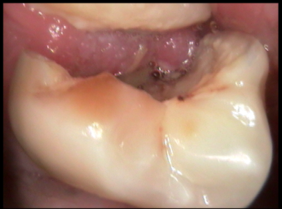

Intraoral Photograhs